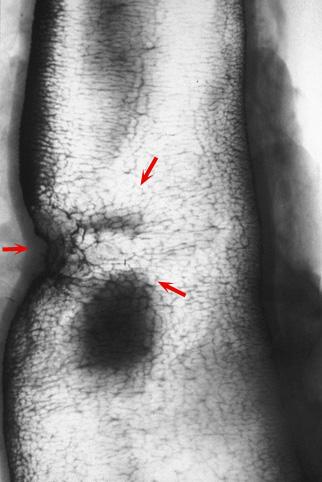

疾病(病理主体)的分类恶性上皮性肿瘤/腺癌

部位(按器官分)大肠/横结肠

检查方法X线

肿瘤的肉眼分类3型(溃疡浸润型)/

肿瘤最大直径25~29

肿瘤的深度mp